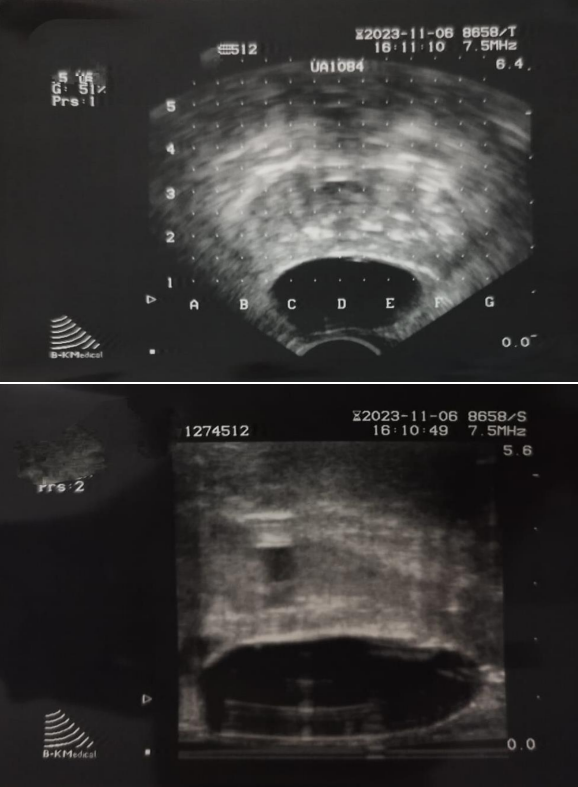

Figure 1: Rectal spacer seen on transrectal ultrasound.

Figure 1